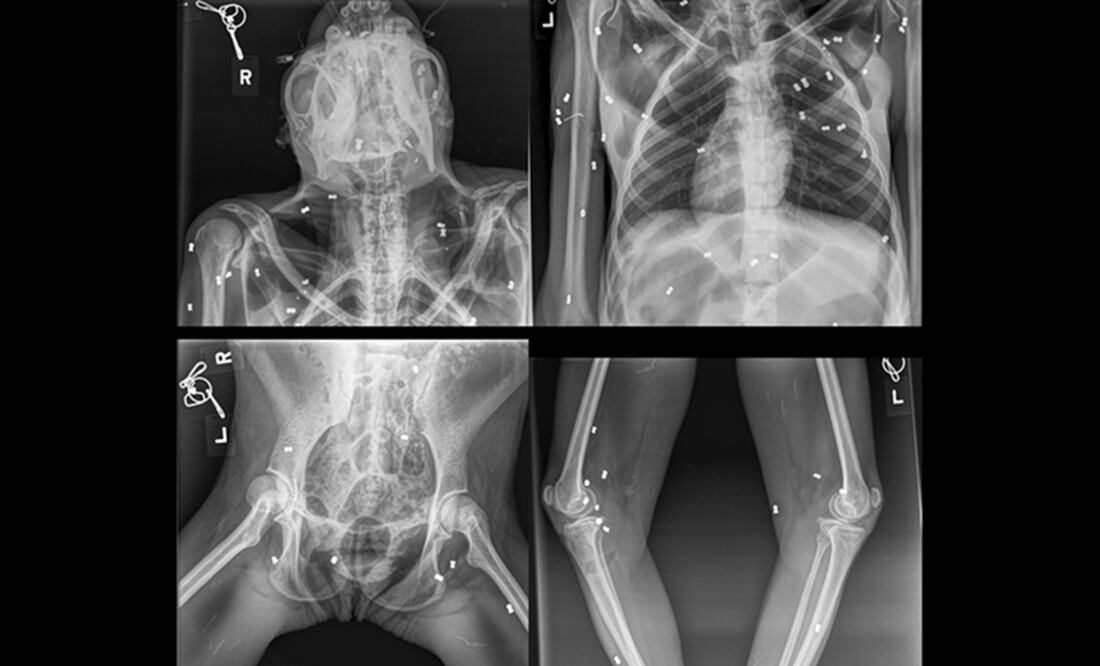

.- Una orangutana fue encontrada con 74 disparos de perdigón en el cuerpo junto a su cría, que murió horas después por desnutrición, en la provincia indonesia de Aceh , anunció este miércoles el Ministerio de Medioambiente de Indonesia.

"La madre presentaba heridas en la mano derecha, la pierna derecha y la espalda, mientras que el bebé de un mes de edad presentaba síntomas de malnutrición", dijo el Ministerio de Medioambiente en redes sociales.

La hembra adulta, de unos 30 años y que recibió el nombre de Hope (esperanza), pudo ser salvada por los veterinarios aunque se encuentra en cuidados intensivos y sigue grave, mientras que la cría pereció y fue enterrada en el jardín del centro de cuarentena.

Foto: Twitter @KementerianLHK